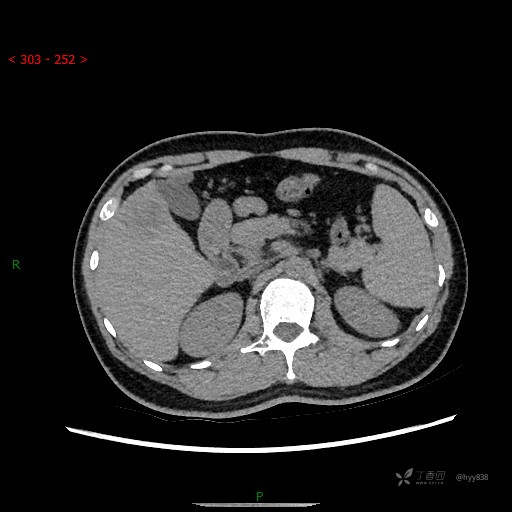

门脉期